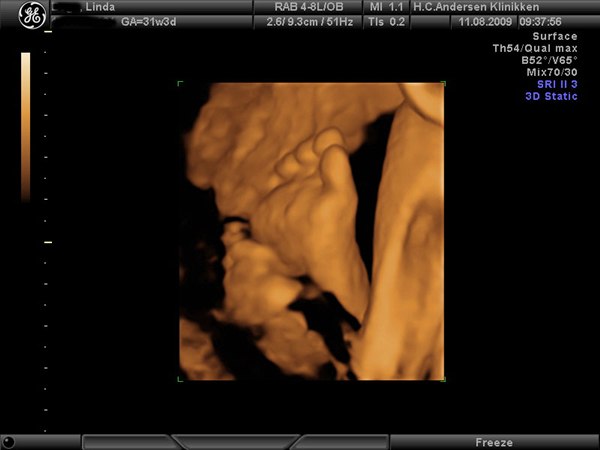

Pige2009

Jeg fik lavet 3D/4D scanning i 32. uge, og det var nærmest som at se den nyfødte baby. Vil klart anbefale dig at vente til du er længere henne

Bemærk at hendes storetå er mindre end de andre tæer - det har hun fra sin far

K.h. Linda